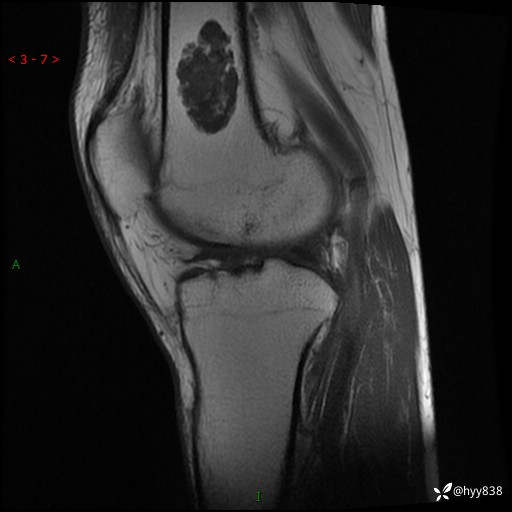

患者性别:男

患者年龄:60岁

主诉:右大腿疼痛不适数月

膝关节平片

MRI

内生软骨瘤 (27)